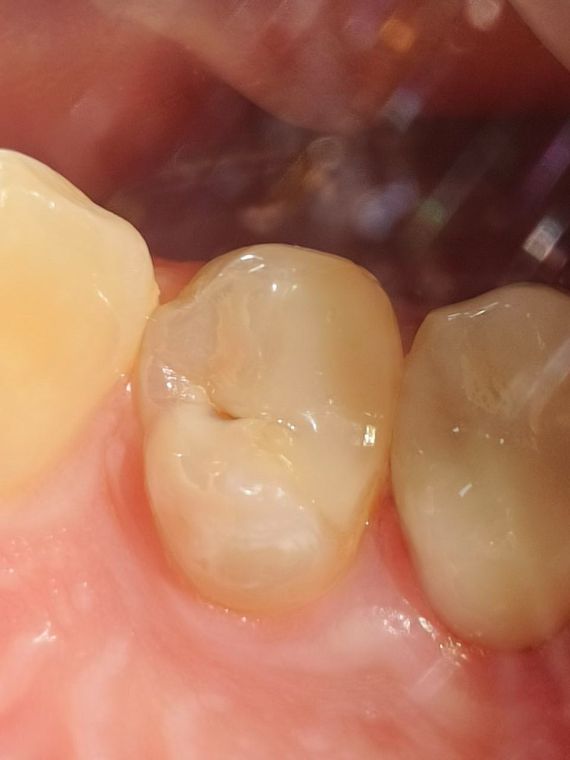

кариозный зуб

На фото представлен скрытый кариес на апроксимальной поверхности зуба

зуб до лечения

Кариес не всегда проявляется как темное пятно, такое бывает в случае поражения зуба с контактной поверхности. Эмаль остается целой, и просто слегка меняет цвет на "белесоватый. Такую полость легче всего увидеть на КЛКТ и рентгене.